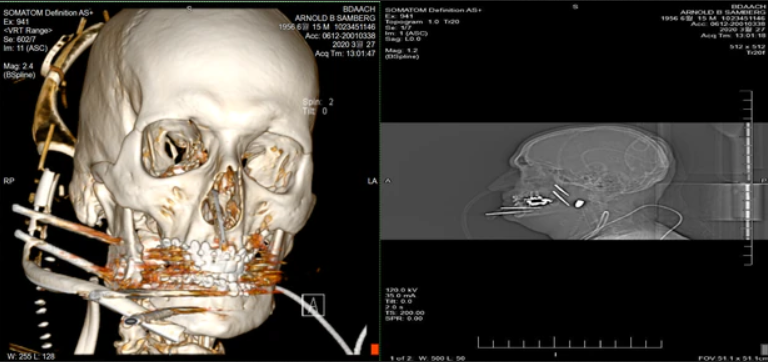

阿諾德·山姆伯格2年前住院時的照片 圖自朝鮮日報

中槍的山姆伯格隨即被送往平澤美軍基地醫院,接受了8個小時的手術,好不容易保住了性命。但隨後的兩年裏,他不斷接受手術和治療,除了種植被擊碎的牙齒,他的大腿和腳腕神經被切斷用於重建下巴周圍的神經,導致他現在正常走路也存在困難,自費承擔的醫療費就超過2億韓元。